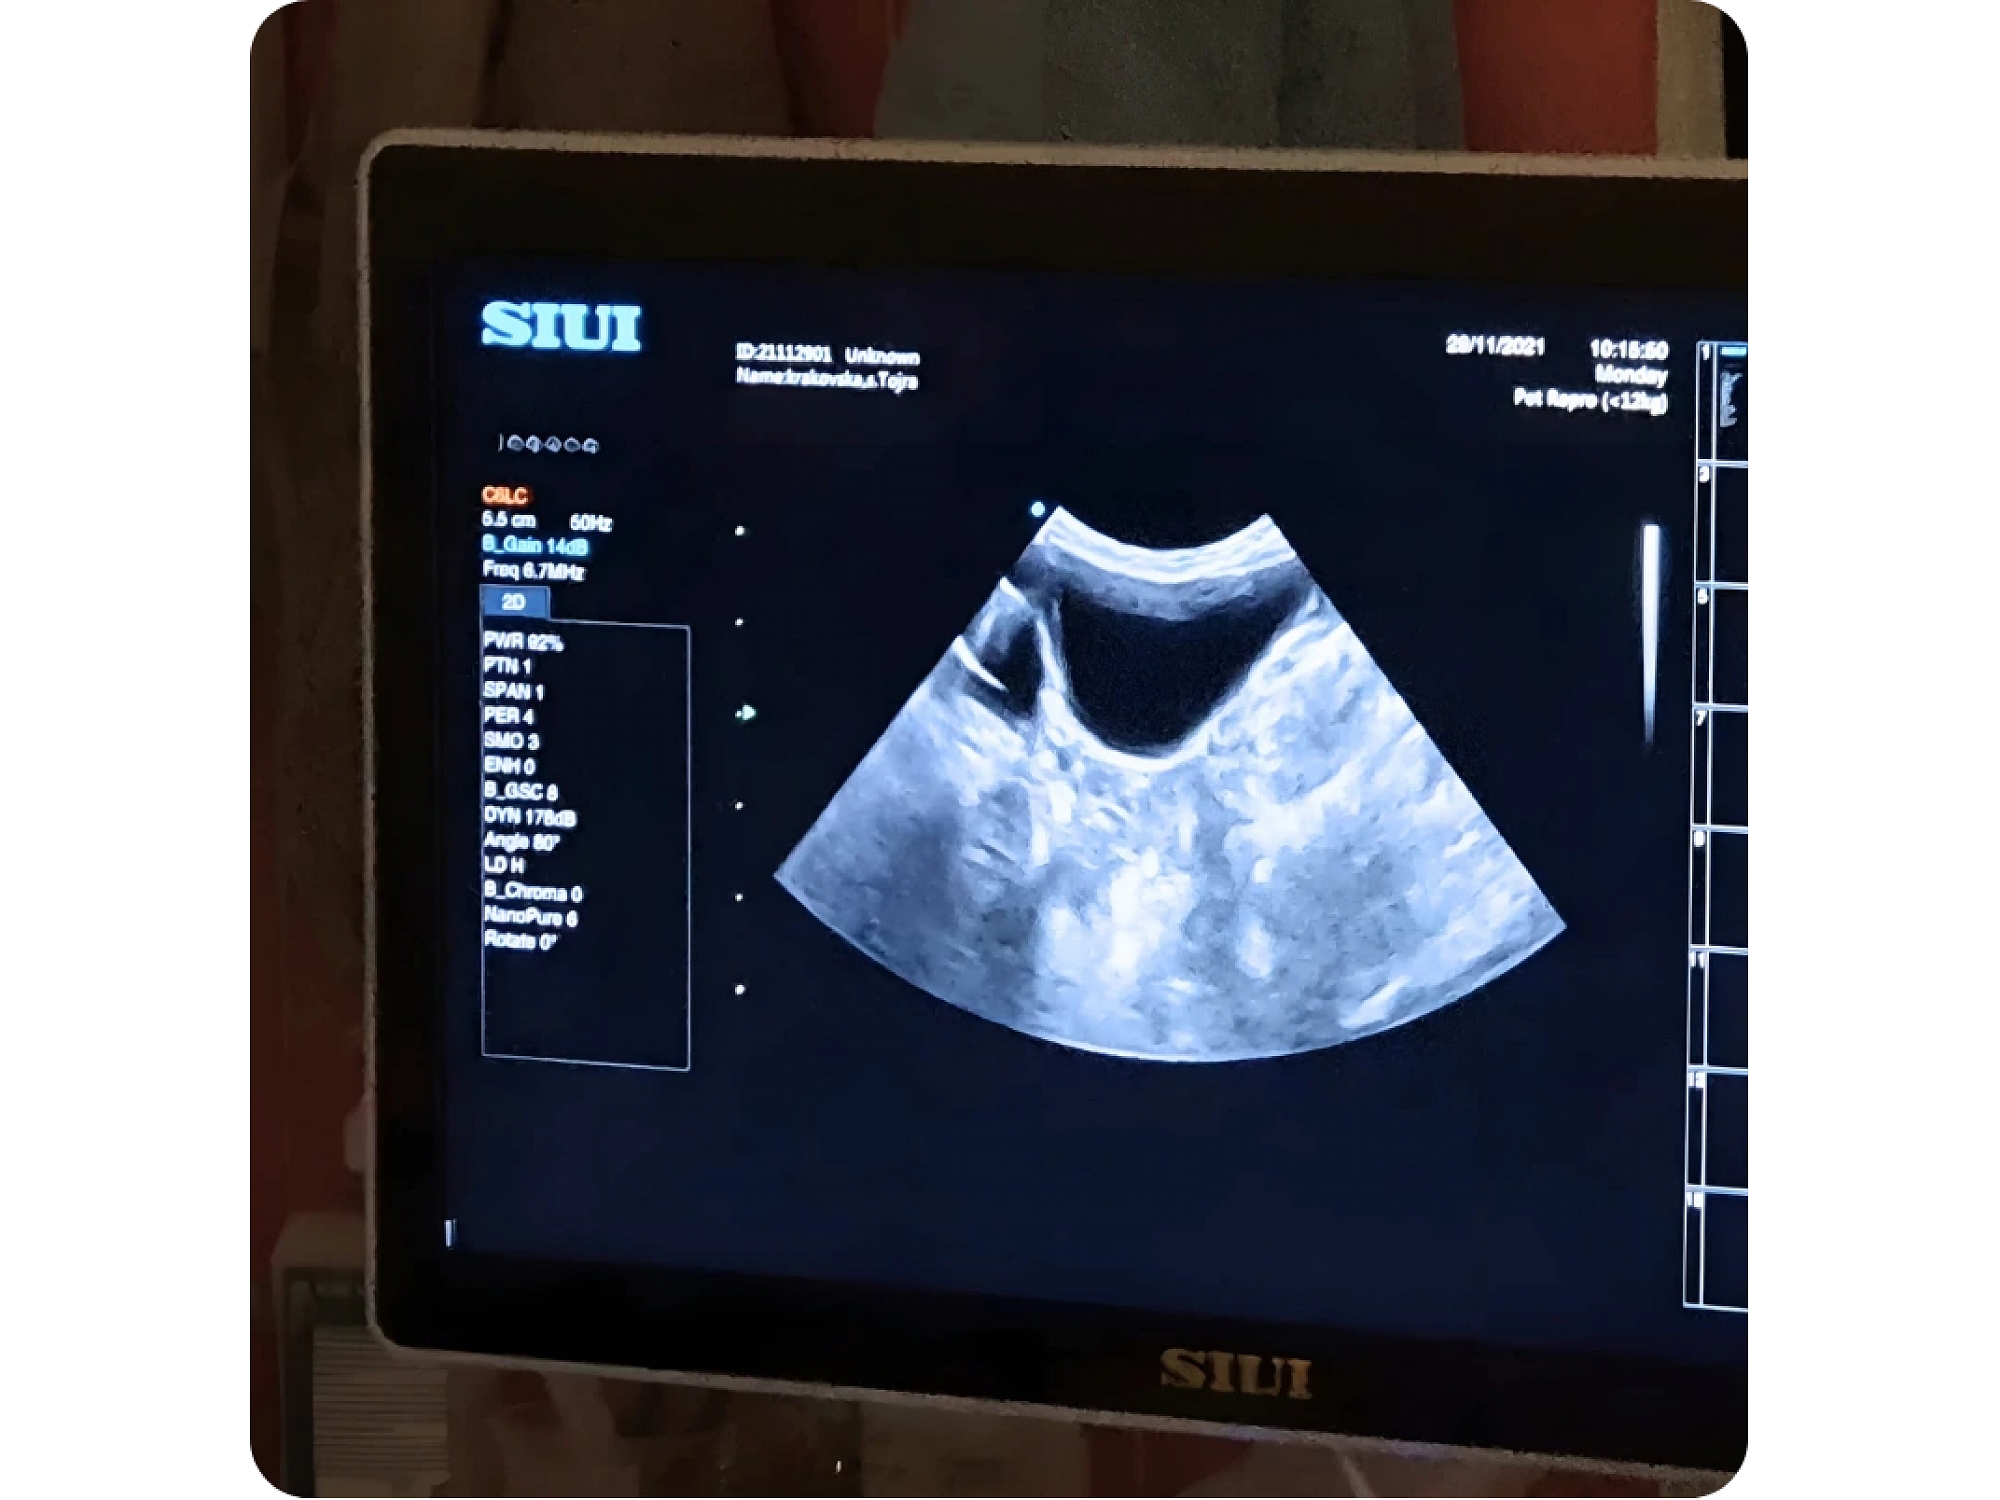

диагностика, лечение, хирургические операции, вакцинация, лабораторные анализы, ультразвуковая диагностика и профилактические меры на животных.